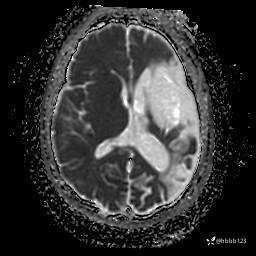

DWI: